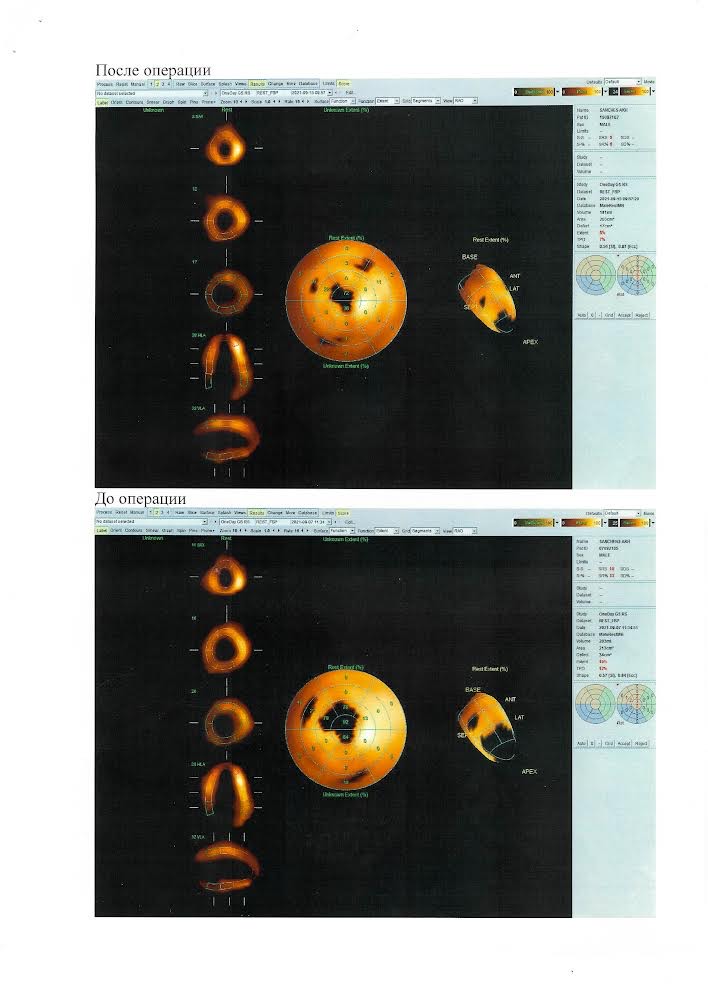

Сотрудники Клиники офтальмологии получили два патента на хирургические методы лечения идиопатического макулярного разрыва.